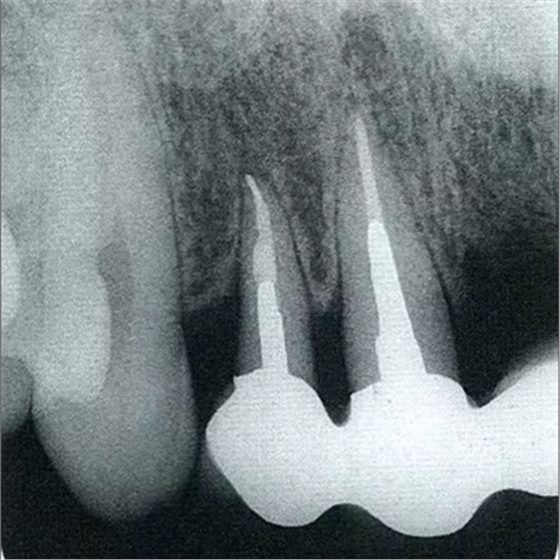

圖10-2 x片顯示的遠中部有垂直性骨缺損。

圖10-10 術(shù)后2年的x片。確認骨水平獲得改善,牙周探診值在2mm以下